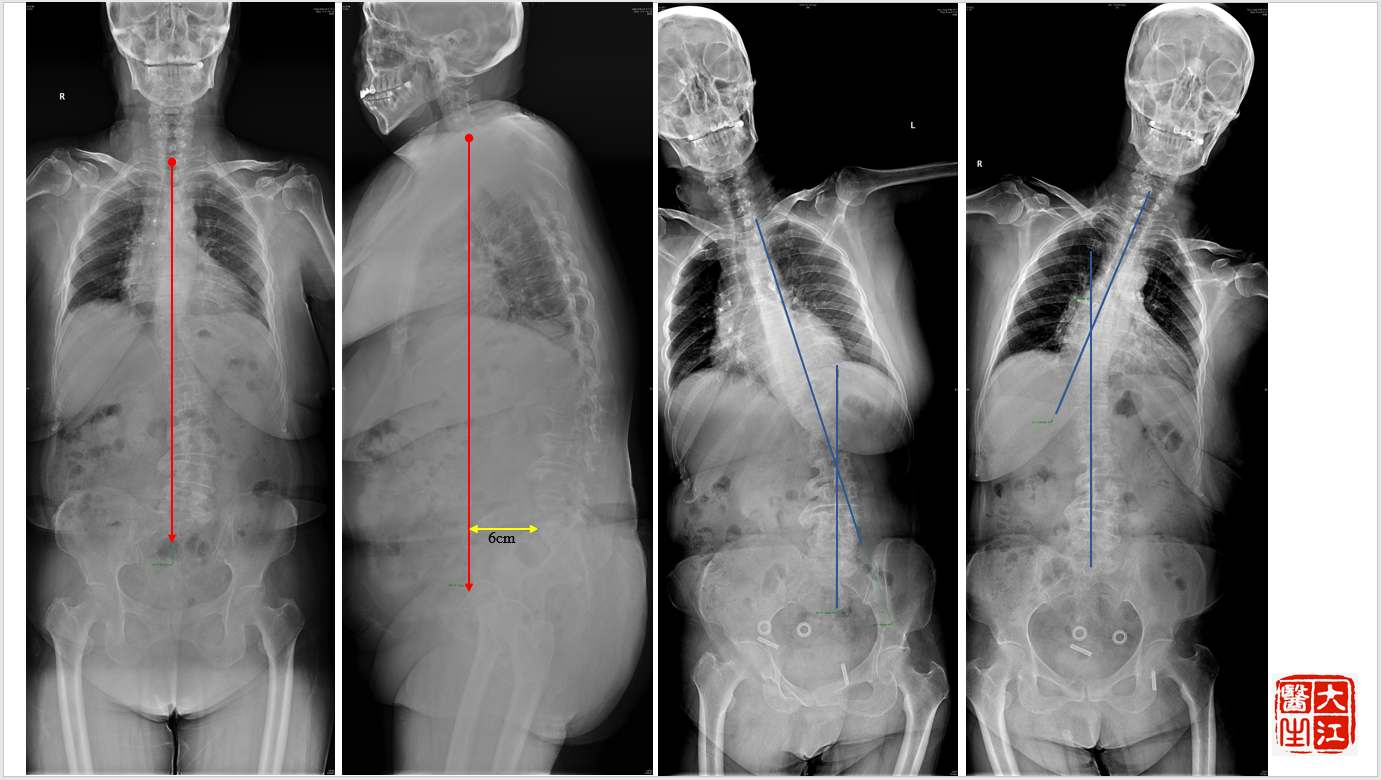

基本情况:女性,77岁,腰痛30年,加重一年,行走困难2月。身高158cm,体重190斤,就诊时轮椅推入病房。

影像检查:

洪毅教授:患者高龄,常年轻度慢性腰痛,本次加重1月余,无下肢神经功能损害,结合患者全长片、核磁体征表现,考虑患者疼痛加重原因为近期出现椎间关节损伤,需关注腰4-5,腰5-骶1节段。腰4-5小关节增生明显,椎间盘高度尚可,不能排除小关节骨关节病。腰5-骶1有ModicII期表现,可能为间盘源性疼痛来源,可进行诊断性封闭治疗。

孙常太教授:患者影像退变性骨关节病表现重,无椎管狭窄。虽有侧凸,但腰2-3,腰3-4侧弯节段可见明显的骨赘形成,稳定性强,腰5-骶1节段椎间盘高度已塌陷,亦较稳定,仅腰4-5节段仍有一定活动度,这就形成腰4-5节段的应力集中,体格检查压痛点与小关节位置亦吻合,需考虑重点关注此节段。

谭荣教授:同意孙教授意见,腰4-5节段动力位显示仍有一定活动度,同时腰4有I°滑脱,证明节段不稳定。病史中患者起身、刚下地时症状重亦支持节段不稳的表现。核磁腰4-5轴位可见明显的小关节病表现,Weishaup分级IV期,亦支持相关诊断。

王炳强教授:患者虽腰椎局部有不稳、侧弯、旋转等表现,但冠状位总体平衡尚可,矢状位有失平衡表现,可能为短期内疼痛加剧导致的,骨盆已参与代偿。若证实疼痛来源,手术完全可以仅进行短节段融合,顺应目前脊柱的形态,无需矫形纠偏等。